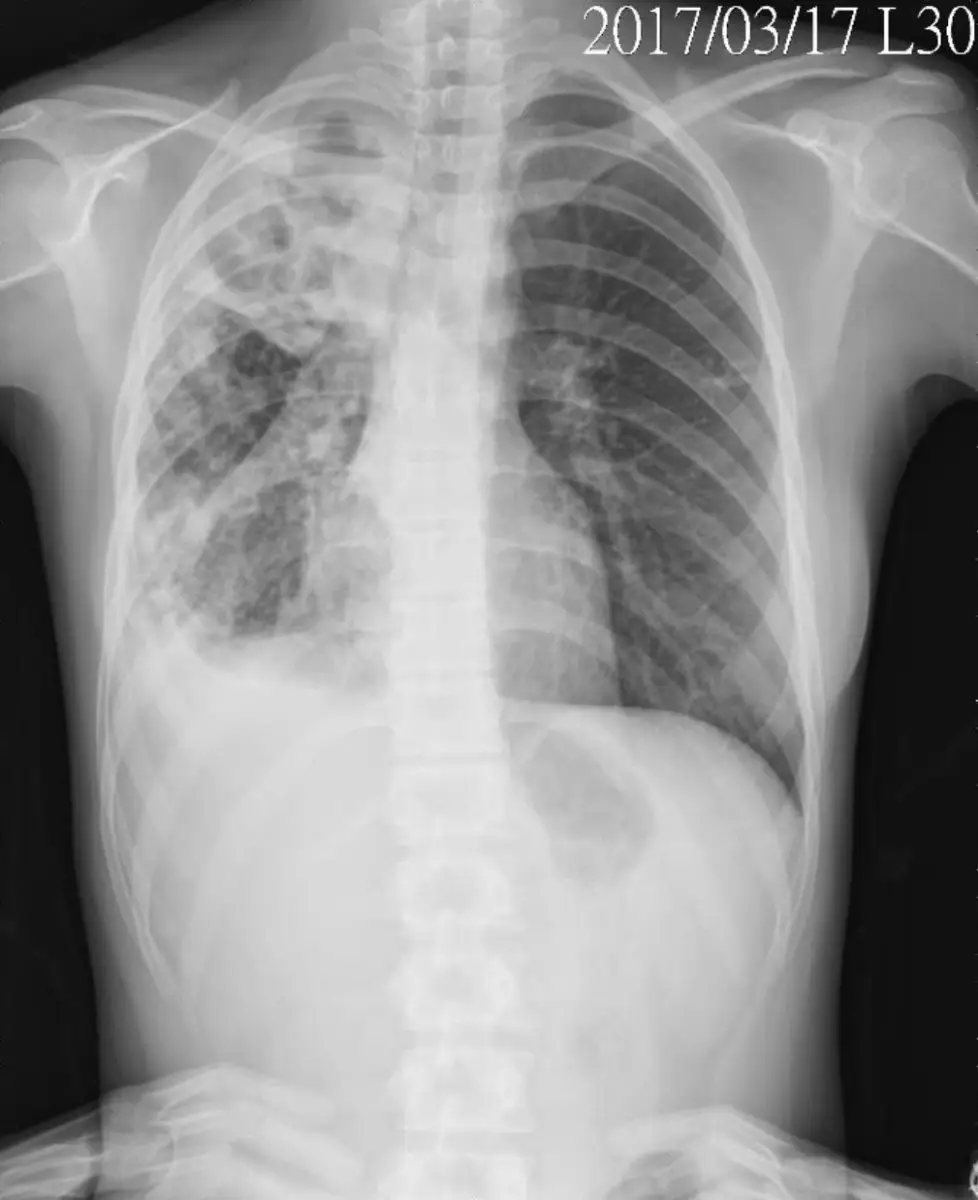

呂同學,18歲,過去健康狀況良好,最近2個月久咳不癒,2週前開始咳嗽有痰、痰帶血絲、發燒、呼吸越來越喘,血壓心跳無異常。住院當日胸部X光片如圖,下列哪一項應優先處置?

• 胸部 X 光:右肺上、中葉大片浸潤並可見類空洞變化,上肺野較常見於 reactivation TB;右下肺界線變鈍可能合併少量胸腔積液。

綜合臨床症狀與影像,首先必須懷疑肺結核,其次才考慮細菌性或其他病原引起之壞死性肺炎。